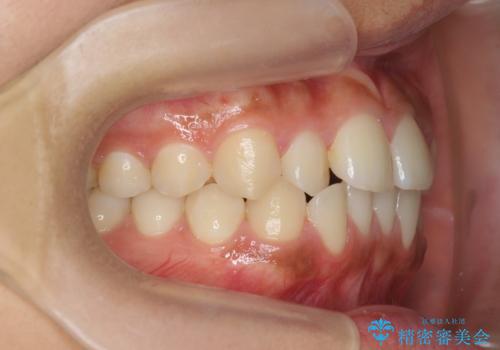

- 前歯のガタつき、上下たがい違いになっている歯並び(クロスバイト)の改善を求めて来院されました。

上下すれ違った噛み合わせはマウスピースでは改善に時間がかかり、またねじれが残ってしまうことも多々見られます。

マウスピース矯正を行う前に、これらの症状の改善の得意なワイヤー部分矯正を行うことで治療期間を短縮し、確実にすれ違いを改善することができます。